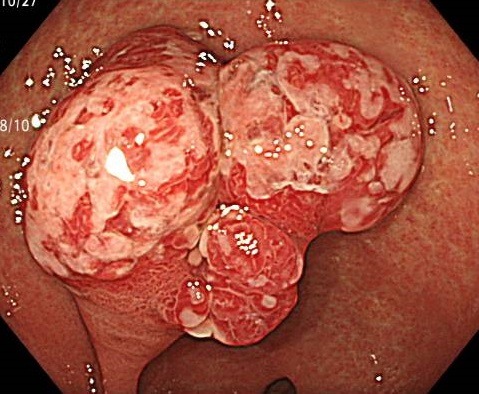

*ピロリ菌陽性の胃内にあった胃過形成性ポリープ

過形成性ポリープは胃底腺ポリープの次に多いポリープです。

主な原因は、ピロリ菌感染や慢性的な胃炎(慢性萎縮性胃炎)によって、胃の粘膜が繰り返し炎症を起こすことです。

炎症が長く続くことで、粘膜の細胞が過剰に増殖し、結果として小さな隆起(ポリープ)が形成されます。

過形成性ポリープの多くは良性で、特に小さいものは治療の必要がありません。

しかし、大きくなるとポリープの表面から出血したり、まれにがん化するケースも報告されています。

特に、2cm以上の大きさや、表面が赤くただれている・びらんがある・形が不整といった特徴を持つポリープは注意が必要です。

また、ピロリ菌感染との関連が非常に深く、除菌治療によって炎症が改善されると、ポリープが縮小または消失することが少なくありません。

このため、ピロリ菌陽性の方が過形成性ポリープを指摘された場合は、まず除菌治療を行うことが治療の第一選択肢になります。

過形成性ポリープは「炎症の結果」としてできる良性変化であり、がんの直接的な原因ではありませんが、炎症を放置するとリスクが増す点は見逃せません。

除菌後も、ポリープが残っている場合や新しいポリープが出てきた場合は、定期的な内視鏡検査での経過観察が推奨されます。